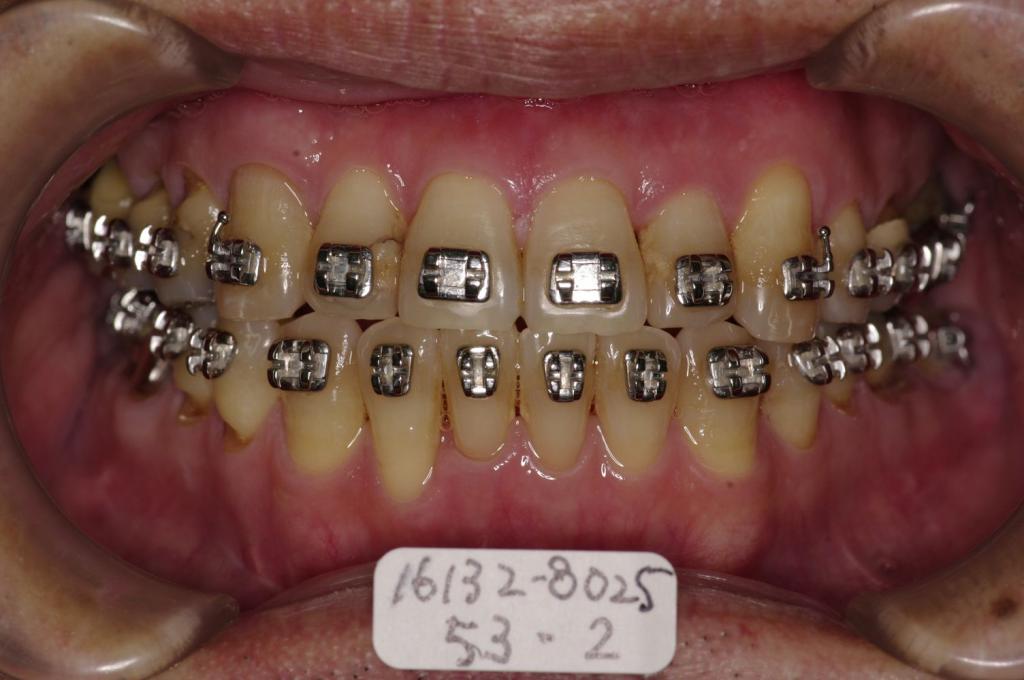

- 顎、顔の歪みの矯正治療